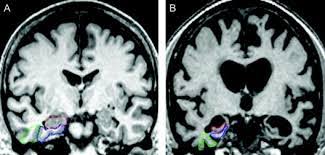

Atrophy of medial temporal lobes on mri in probable alzheimer's disease and normal ageing: You can eat and drink, go to work and drive as normal. Ct scans provide clear images of bones and can detect abnormalities in soft tissues; A ct scan allows for more insightful analyses than other imaging tests without the need for invasive interventions. Ct scan indices of hippocampal atrophy are highly associated with alzheimer disease, but the specificity is not well established. Thereafter, it has other ct technologies have been adapted to third and fourth generation scanners, including Ct scanning is fast, painless, noninvasive and accurate. Differences between normal and abnormal tissue is often clearer on an mri image than a ct. Diagnostic value and neuropsychological correlates. If a contrast was used, you may be advised to wait. Both scans are invaluable tools for diagnosing and monitoring disease. What is the difference between ct scan vs mri scan. It also helps to help.

A ct scan allows for more insightful analyses than other imaging tests without the need for invasive interventions. Movement can blur the image, so you'll be asked to stay very still. A ct scan can help diagnose many types of cancer. Ct scans have advantages in viewing anatomical structures. Ct scan indices of hippocampal atrophy are highly associated with alzheimer disease, but the specificity is not well established.